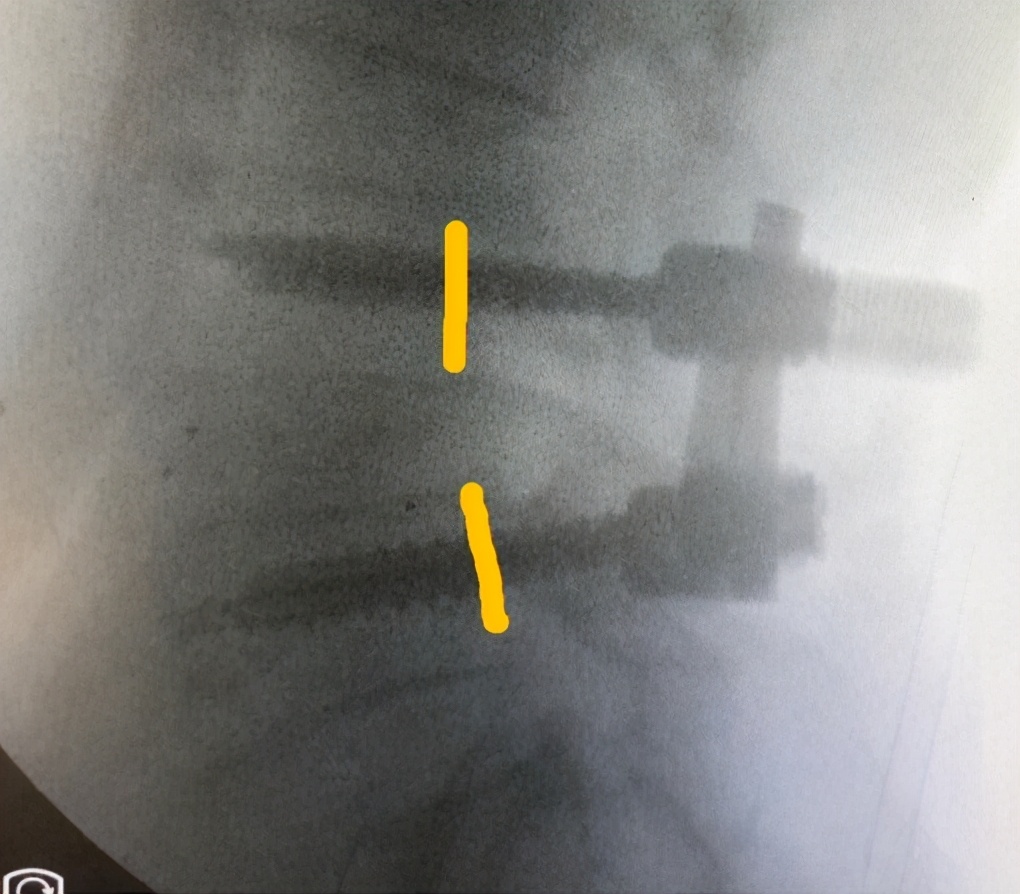

术中

术后

1.疼痛缓解

2.基本可以正常行走

VAS疼痛评分:1分;ODI残疾指数:20%

影像